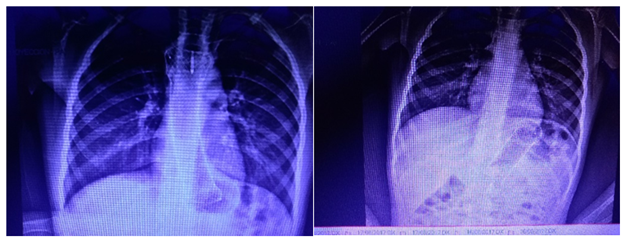

Figure 4 A. Metalic expandible thoroughly covered esophagus stent in its correct place on esophagus, march-24-18. B. Migrated to stomach on june-8-2018.